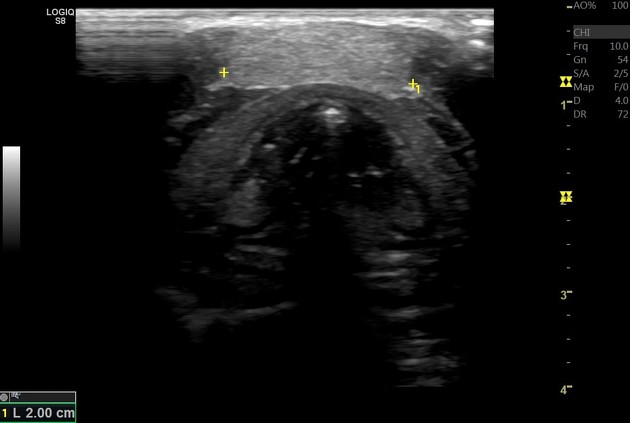

Figure, Ectopic thyroid] - StatPearls - NCBI Bookshelf Ectopic Thyroid - Endocrinesurgery.net.au Sites of ectopic thyroid localization along its descending pathway. | Download Scientific Diagram Ectopic thyroid tissue in the head and neck: a case series | BMC Research Notes | Full Text | Ectopic Thyroid